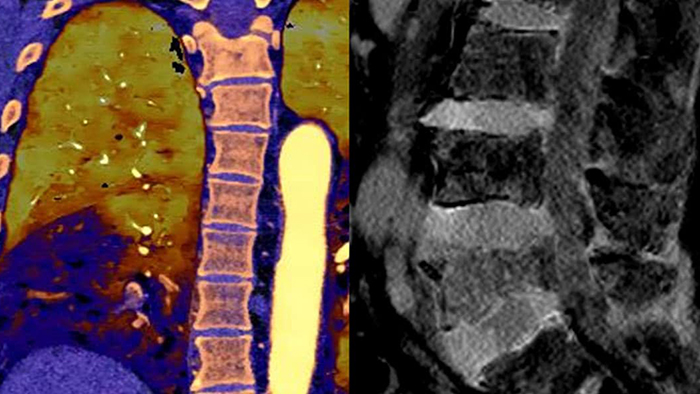

Unlike traditional CT images, spectral-detector CT images capture spectral information 100% of the time —without special planning or set-up. That means you can analyze the spectral data in any image retrospectively, using a variety of spectral viewing tools. You can, for example, adjust the monoenergetic level or get Zeffective maps.

Can you see the difference?

Move the slider to reveal spectral results when compared to conventional CT.

Conventional CT Spectral result

Spectral detector simultaneously absorbs and differentiates high and low energy from a single polyenergetic X-ray beam. Spectral results are acquired within a single scan without the need for special modes.

Detector-based spectral CT simultaneously absorbs high and low energies in the same time and space.